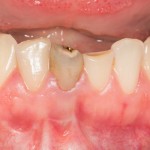

Рекомендации по установке имплантов. Для всех. Часть II.